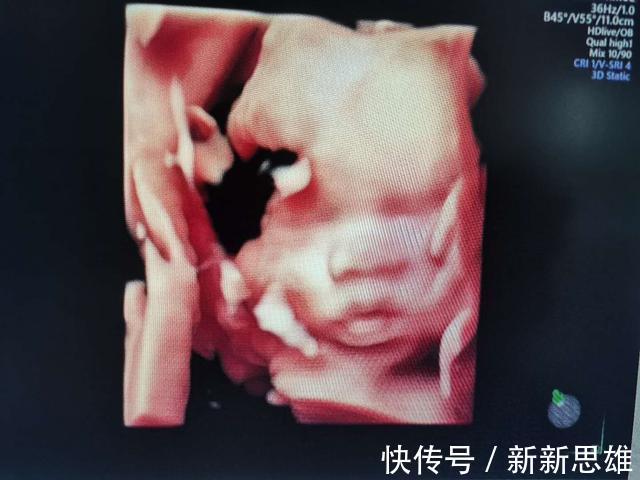

28-32周:是胎儿的小排畸,因为胎儿是一个不断发育完善的过程,需要不断发育不断检查,并不是一次通过就代表以后都没有问题了,不是这样的,这个时期也是给胎儿拍照的好时机,可以看清胎儿的面部成像。四维彩超可以更加清晰立体的看到胎儿的面部表情,拍出来的照片几乎就是宝宝刚出生后的样子,真的很神奇,我们也可以给宝宝留一个相册,这样也能留下一个美好的回忆。